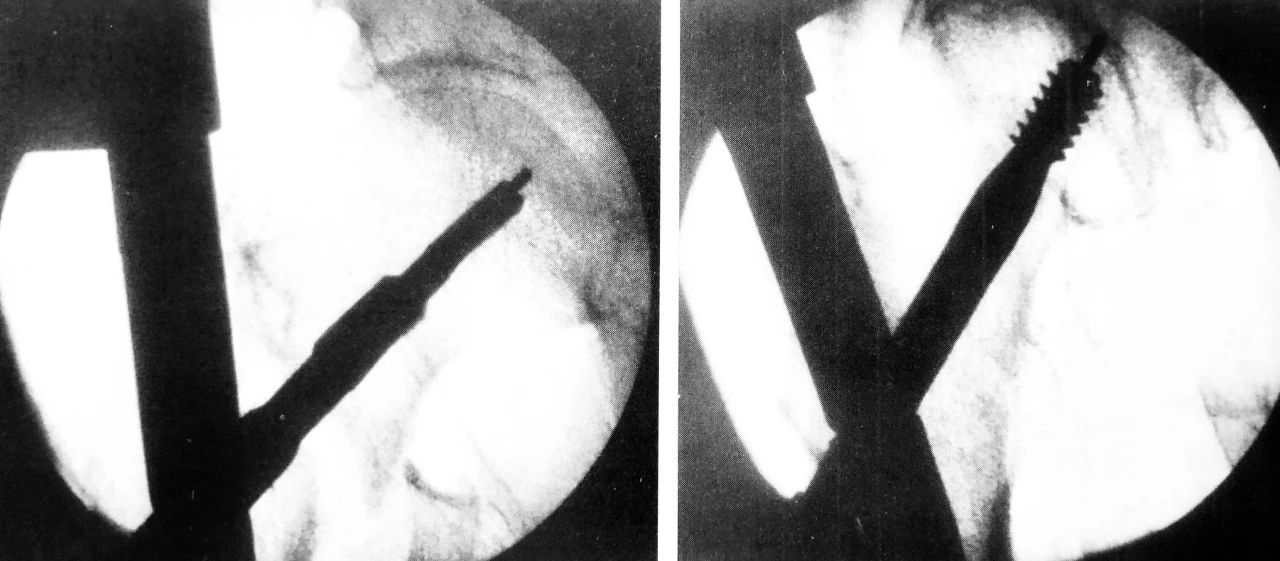

C 形臂下操作步骤,尖端开髓、插入导针

扩髓、主钉置入